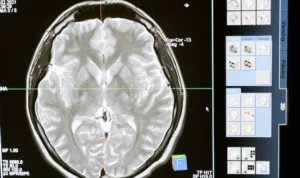

The brain is one of the most complex and vital organs in the human body. It controls our thoughts, emotions, actions, and coordinates various bodily functions. Maintaining a healthy brain is essential for overall well-being and quality of life. World Brain Day aims to encourage people to adopt healthy lifestyle habits that support brain health, such as engaging in regular physical exercise, eating a balanced diet, getting sufficient sleep, and engaging in mentally stimulating activities.

Another critical aspect of World Brain Day is to raise awareness about neurological disorders, which can affect individuals of all ages and backgrounds. Neurological disorders encompass a wide range of conditions, including epilepsy, Alzheimer’s disease, Parkinson’s disease, multiple sclerosis, migraine, and many others. These disorders can have a profound impact on individuals’ lives, affecting their cognitive abilities, motor skills, and overall functioning.

In addition to raising awareness, World Brain Day also emphasizes the importance of brain research. Scientific advancements in neuroscience play a crucial role in understanding the complexities of the brain and developing new approaches to prevent, diagnose, and treat neurological disorders. Funding and support for brain research are essential to make further progress in the field of neuroscience and improve the lives of those affected by brain-related conditions.